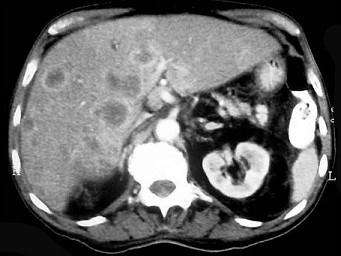

问题 继发性肝癌诊断的关键是 ( )

选项 A、行CT检查 B、测定血清甲胎蛋白 C、行肝动脉造影检查 D、行放射核素扫描 E、查清原发癌灶 单选题

答案 E